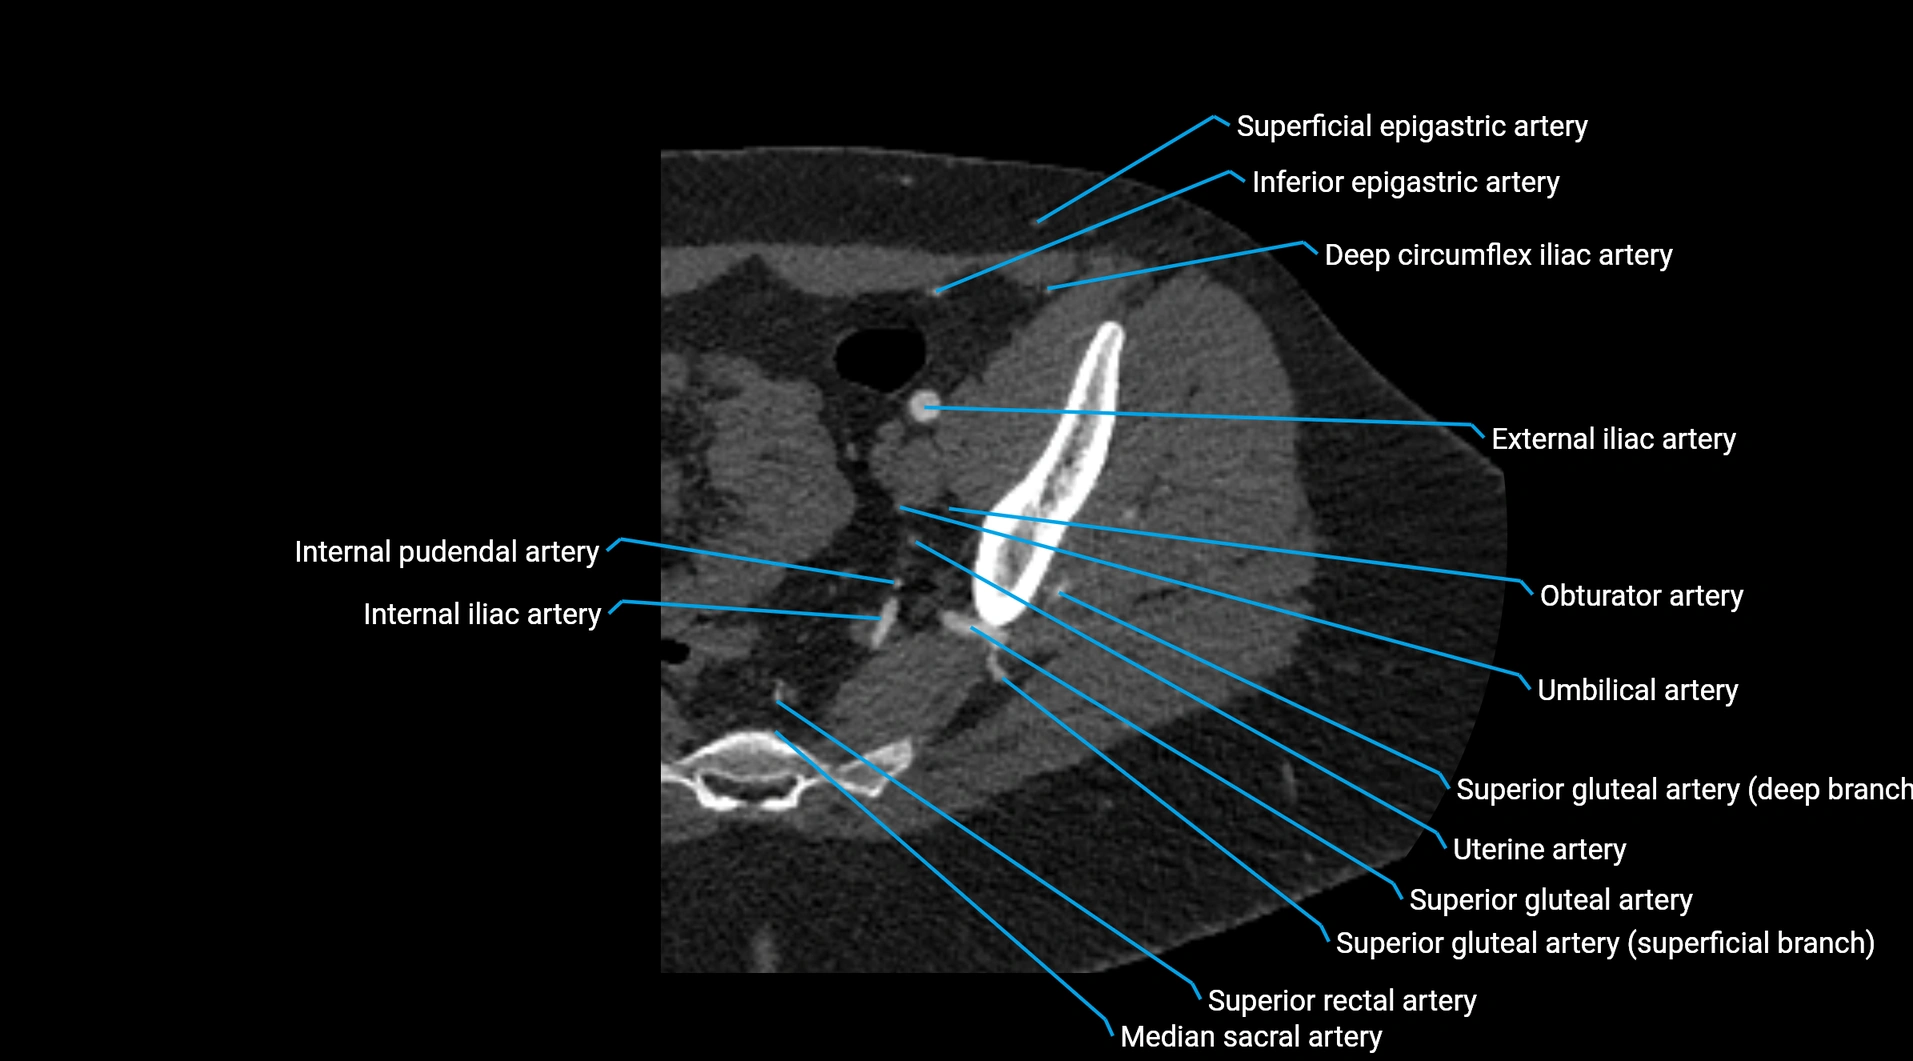

Contrast-enhanced CT (CTA):

• Gold standard for abdominal aortic imaging

• Provides excellent detail of lumen, wall, aneurysm, thrombus, and branch vessels

• Multiplanar and 3D reconstructions help in aneurysm measurement, stent graft planning, and dissection evaluation

• Detects acute rupture, traumatic injury, or occlusion with high sensitivity